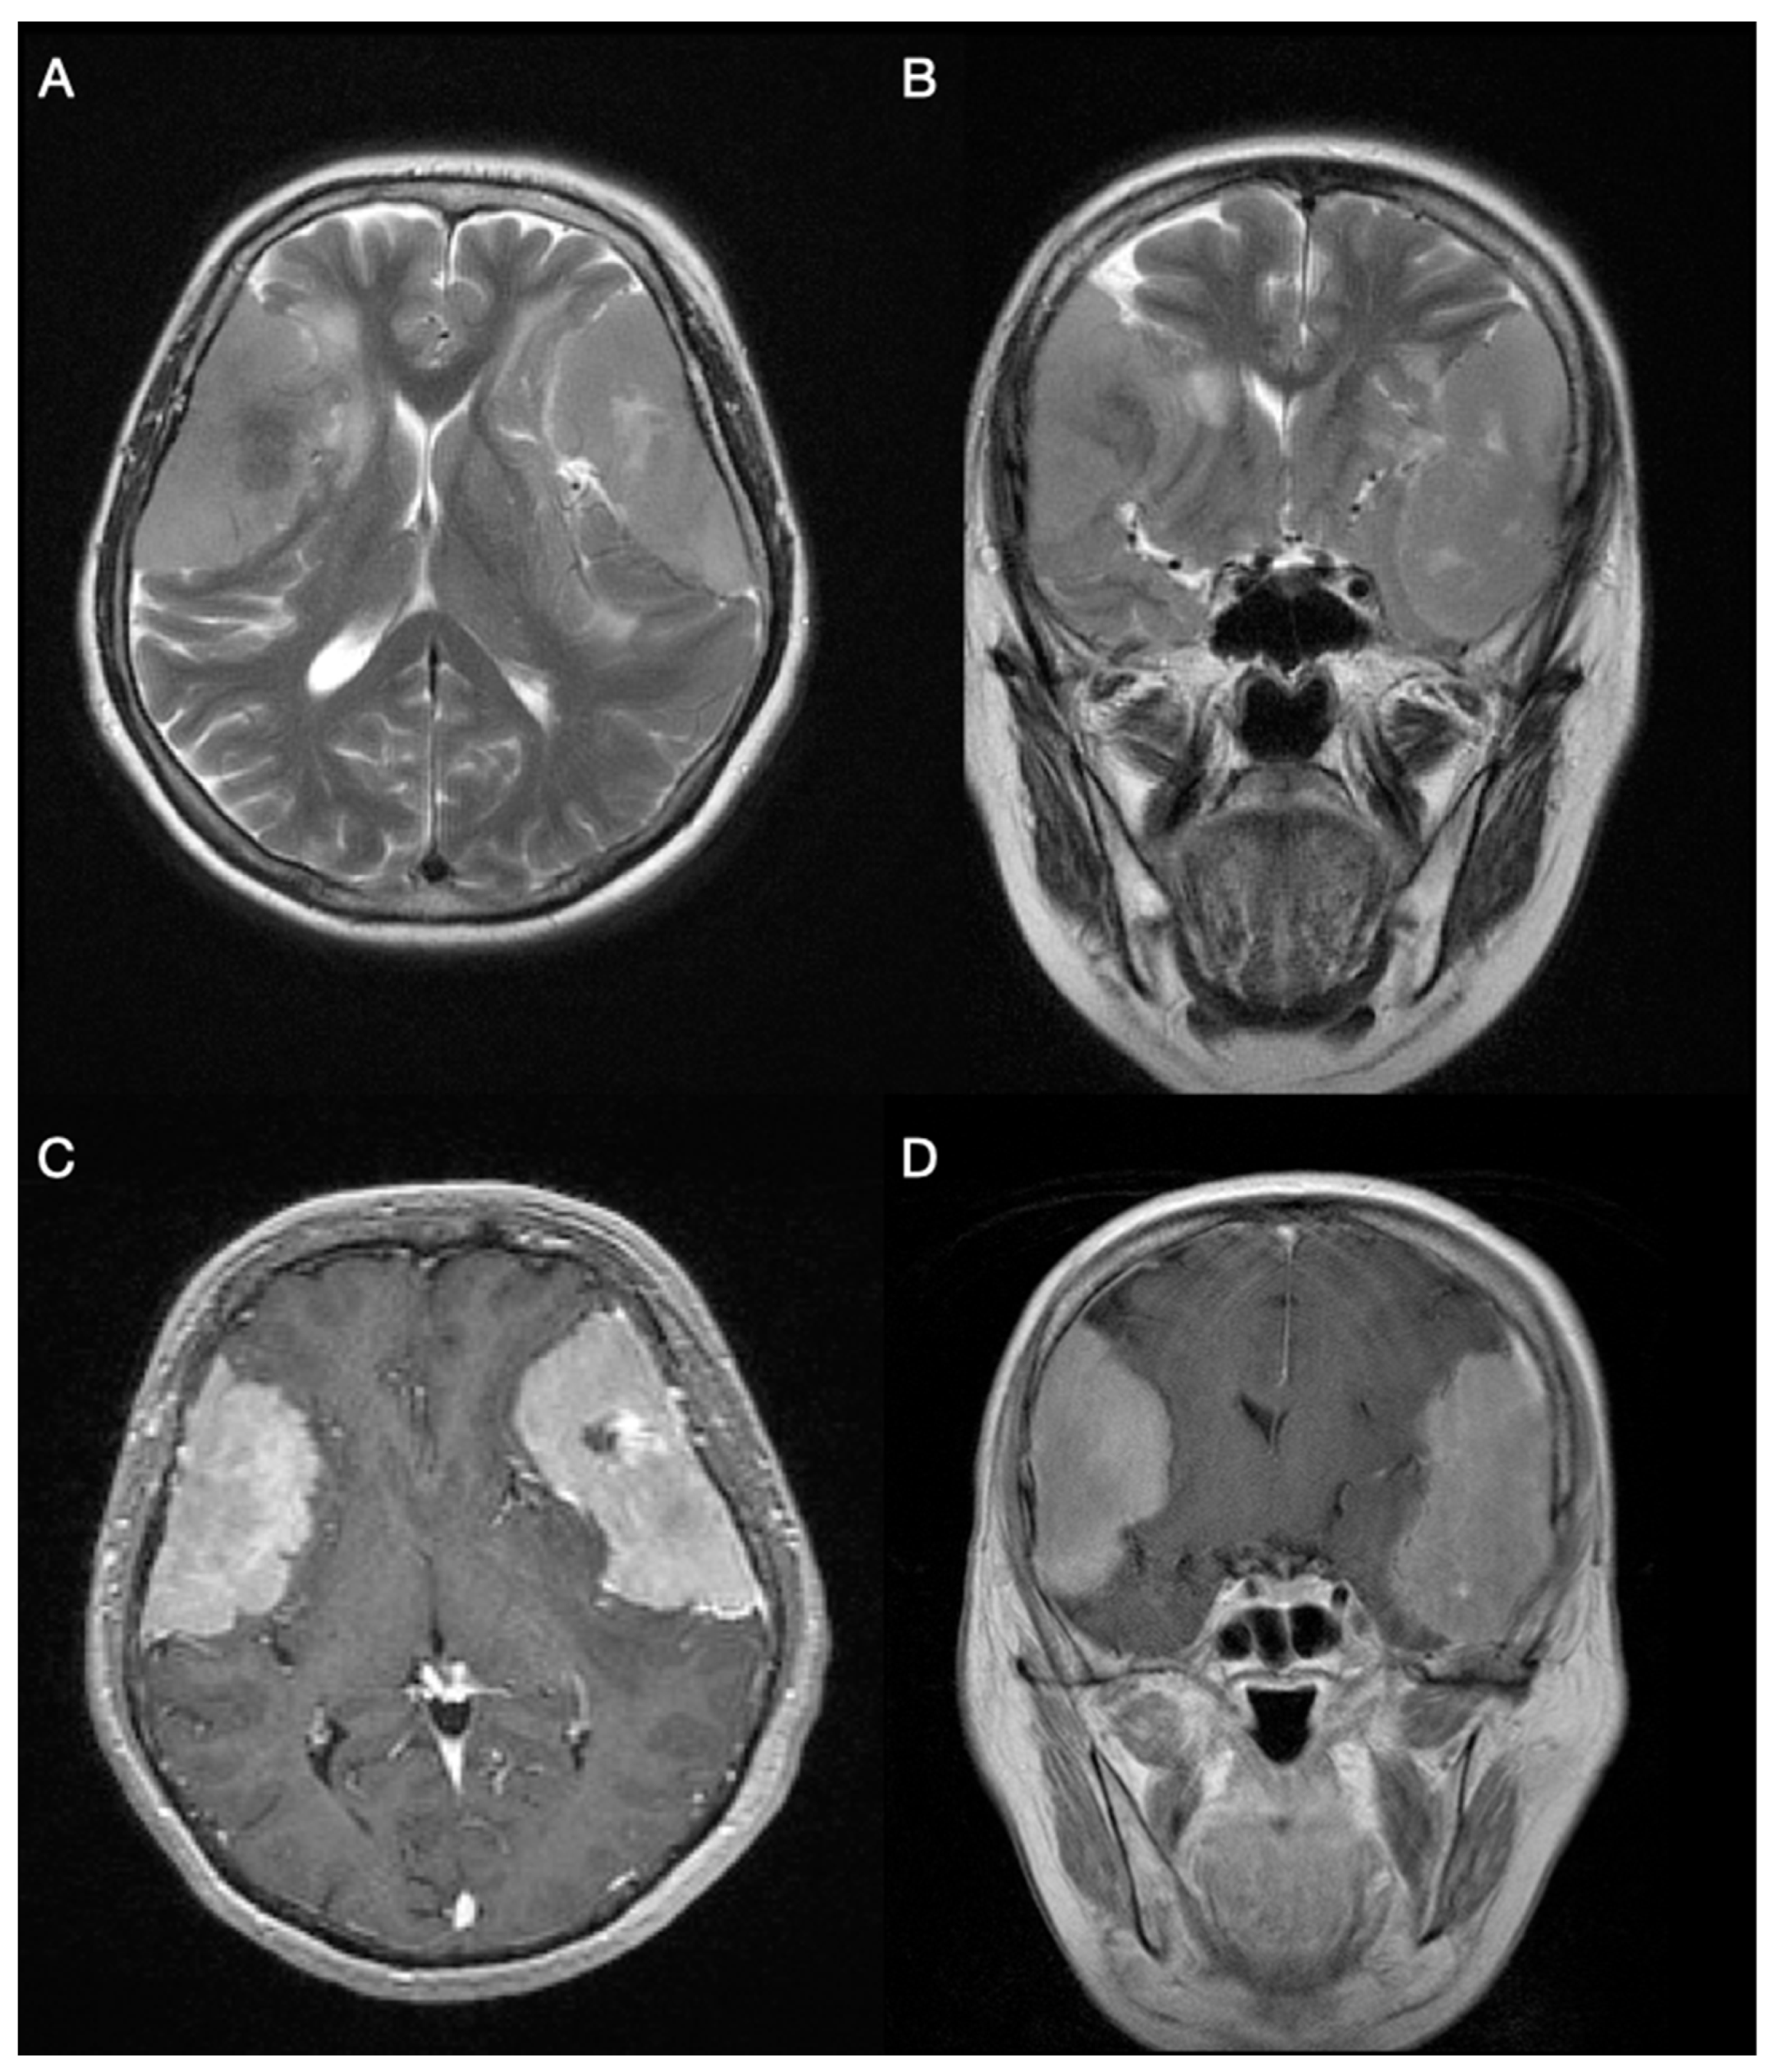

| Meningoma #1 | |

| Type | Grade I meningothelial meningioma |

| Location | Left frontotemporoparietal region |

| Consistency and dimensions | Soft consistency with dimensions 7.5 × 6 × 3 cm |

| Mitosis | Nuclei of tumor cells were hypochromatic. Only 1 mitosis found in 10 consecutive high-power fields. |

| Histological description | Nest configurations of meningothelial cells were placed in pseudosyncytial formation. Minor centers of necrosis were observed. Connective tissue, surrounding the tumor, was partially enlarged. A few psammoma bodies were spotted. On the margins of the specimen, there was a sharp transition from tumor cells to healthy brain tissue. |

| Meningoma #2 | |

| Type | Grade II atypical meningioma |

| Location | Right frontotemporoparietal region; tumor attached to dura |

| Consistency and dimensions | Grey, solid consistency with dimensions 7 × 4 cm |

| Mitosis | Maximum of 5 mitosis in 10 consecutive high-power fields were found |

| Histological description | The tumor was built of meningothelial cells forming a pseudosyncytial structure. Hypercellular areas with clear margins between cytoplasmic membranes were spotted. There was no necrosis inside the tissue. Hyalinization and calcification of connective tissue were seen in some areas. A sharp transition from tumor cells to healthy brain parenchyma tissue separated by layers of connective tissue. |